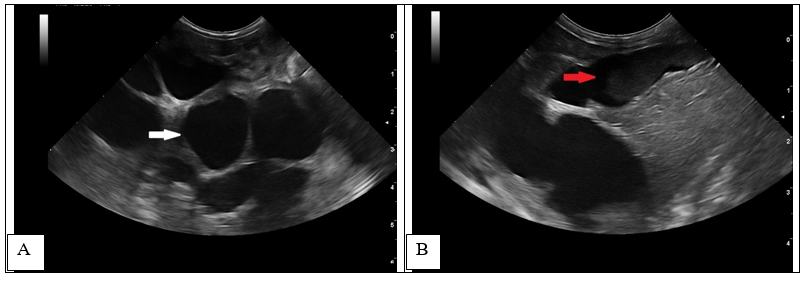

A follow-up ultrasound performed 4 weeks after the initial examination, revealed an increase in the distention of the intrahepatic bile ducts (> 7 mm) (Figure 2A-white arrow) with echogenic material formation within the ducts (Figure 2B-red arrow), thickening of the gallbladder wall (1.4 mm)10,27 and multilayer pattern (double rim aspect).

Figure 2 1-month follow-up ultrasound scan at the level of the liver (transverse and longitudinal images).

Increased dilatation of the intrahepatic bile ducts, with secondary compression of the local vasculature (A). Dependent echogenic debris is seen within the tubular bile ducts. Following the normal architecture of the bile ducts (localized in the proximity of the liver vasculature), the portal branches were difficult to visualize, causing the intraluminal portal vein sign16,27 (dilated ducts surrounding the portal vein) (Figure 3).

An ultrasonographic re-examination performed at 4 weeks showed a decrease in the intrahepatic bile duct size, however, transversal intraluminal septae at the level of the intrahepatic biliary tree were noted (Figure 5-white arrow). Portal flow velocity was recorded within normal limits, with regular flow (Figure 6).

Figure 5 1-month follow-up ultrasound scan. Transverse image of the intrahepatic biliary tree. Septal formation (white arrow) was seen bridging the walls of the hyperechoic duct. Echogenic to hyperechoic bile was seen at the level of the left and central liver.